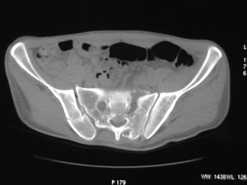

Диагноз : Сочетанная травма. ЗЧМТ. Перелом свода черепа. Ушиб головного мозга.Разрыв лонного и крестцово-подвздошного сочленений с нарушением целостности тазового кольца, с массивной забрюшинной гематомой и пропотеванием в брюшную полость. Перелом 10 ребра справа, осложненный гемопневмотораксом справа, правосторонней пневмонией на фоне ушиба правого легкого. Шок 3-4 ст. Больной поступил в отделение 07.03.2005г. в 16.00 в экстренном порядке через 30 минут после автодорожной травмы.Доставлен КСП. При поступлении состояние больного крайне тяжелое, явления травматического шока, А/Д-80/60 мм.рт. ст. ЧСС-120.В экстренном порядке поднят в операционную, интубирован, совместно с диагностическими мероприятиями лечение шока.При осмотре выявлены перелом 10 ребра справа, разрыв лонного и правого крестцово-подвздошного сочленений. Имеется линейный перелом теменной и височной костей слева с переходом на основание. Диагностическая лапароскопия 07.03.2005г. в 16.30-массивная забрюшинная гематома малого таза.Оставлена контрольная, дренажная трубка.Учитывая кровь в моче произведена цистография - данных за разрыв мочевого пузыря не найдено. Больной переведен в реанимационное отделение.За 08.03.2005г. из брюшной полости выделилось до 1500,0 мл, крови, часть крови реинфузирована. 08.03. в 06.30 наложен торокоцентез справа,удалено 100,0 мл. крови и 200,0 мл. воздуха .. Учитывая продолжающеееся кровотечение в брюшную полость из перелома костей таза, для исключения возможного разрыва внутренних органов 09.03.2005г. произведена Видеолапароскопия., на которой повреждения органов брюшной полости не выявлено.Одновременно произведен шов лонного сочленения проволокой и винтами, с одномоментным наложением стержневого аппарата на кости таза, с целью уменьшения кровотечения из разрывов тазовых сочленений, дренирование гематом. В последующем состояние больного оставалось тяжелым. 10.03.наложена нижняя трахеостома.Далее неоднократно производилась лечебно-диагностическая ФБС.С 10.03 выявлена правосторонняя плевропневмония. КТ головного мозга от 10.03-субарахноидальноекровоизлияние.Срединные структуры не смещены. КТ-контроль от 15.03-открытая моновентрикулярная гидроцефалия4 желудочка. Полисинусит. Постепенно состояние больного медленно прогрессировало к улучшению.С 24.03 переведен на самостоятельное дыхание, а 09.03 переведен в травматологическое отделение.Аппарат стержневой снят из-за перелома стержня (раскрутил больной самостоятельно).После госпитализации в наше отделение проведено дополнительное обследование Рентгекнография, КТ.Хотелось бы услышать Ваше мнение о дальнейшей тактике.-- С уважением, Leonid

Углядел билатеральное повреждение таза. Имеется вертикальная нестабильность со стороны перелома боковой массы крестца, ротационная с контрлатеральной стороны - чрезподвздошный разрыв кп сочленения. Разрыв лона, запирательные отверстия вроде целы.

DS. на сегодняшний день: Вертикальная двусторонняя нестабильная деформация таза, неправильно срастающийся перелом боковой массы крестца слева, срастающийся перелом крыла правой подвздошной кости, застарелый частичный разрыв правого кп сочленения, застарелый разрыв лонного сочленения.